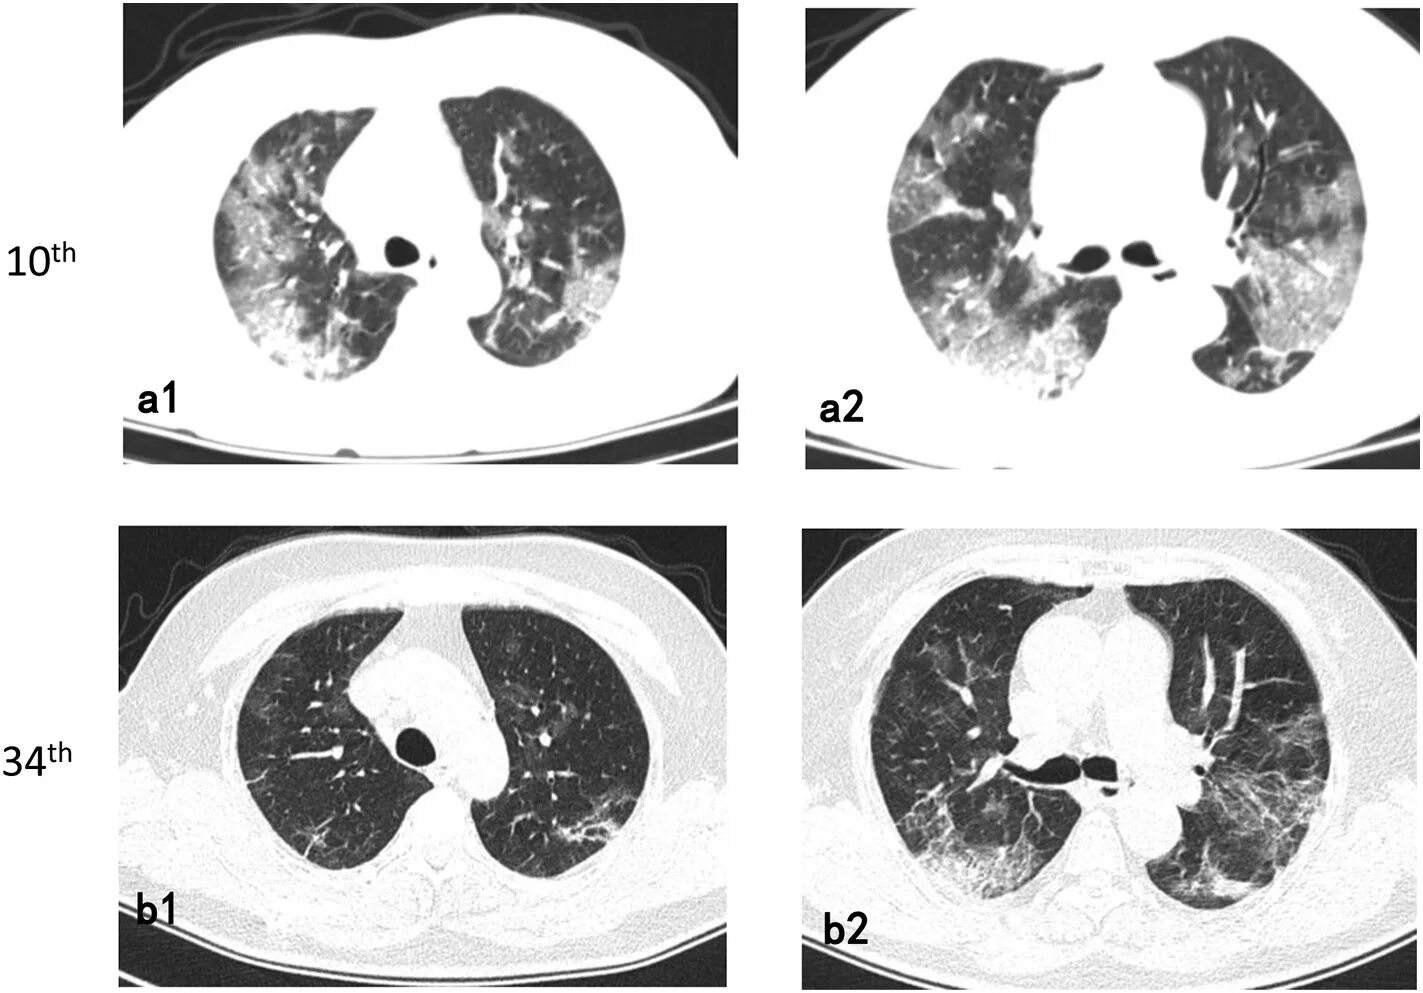

Опасно делать кт